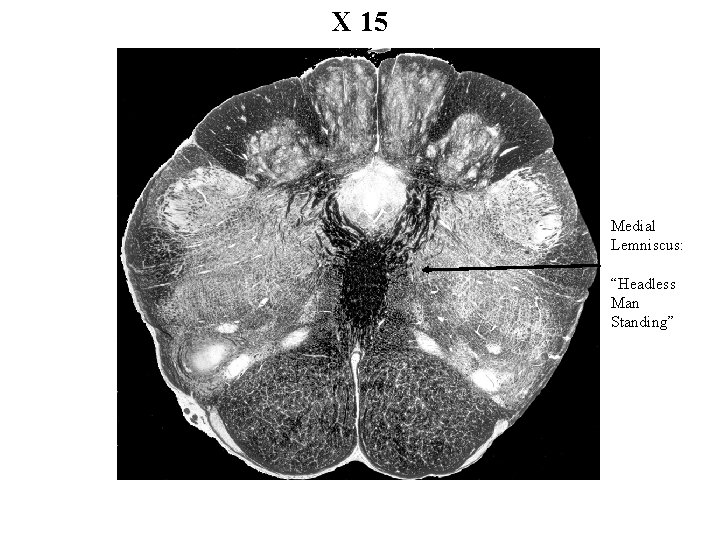

X 15 Medial Lemniscus: “Headless Man Standing”